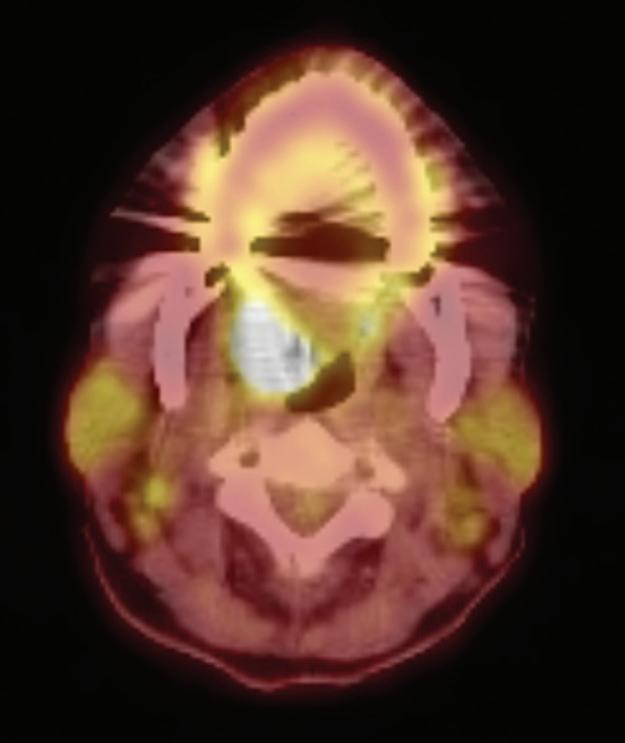

Multidisciplinary approach to diagnosis and management of lymphadenopathy in a patient with mucous membrane pemphigoid: a case report

Heba Turkstani

Eric T. Stoopler

Temitope T. Omolehinwa

Eman Alamodi

Mel Mupparapu

Cover image inspired by: Multidisciplinary approach to diagnosis and management of lymphadenopathy in a patient with mucous membrane pemphigoid: a case report, on p. 48